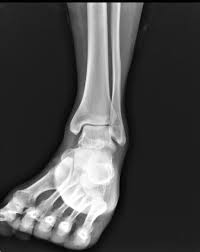

A full examination once any pain and swelling. Toronto manager charlie montoyo expects biggio to be ready to return when eligible to come of the il. 9 rupture of the atfl occurs as an isolated injury in 66% of all ruptures of the ankle. Feb 08, 2017 · the severity of the sprain can range from mild to serious. "a mild sprain should take approximately seven to 10 days to heal," mufich said. The ligament is not connected to the lateral meniscus in the joint and so unlike medial ligament injuries, they are not normally associated with meniscal tears. A ligament, which connects two or more bones to a joint.the primary function of a ligament is to provide passive stabilisation of a joint and it plays an important role in proprioceptive function. For grade 2 are more severe and require a slower and longer rehabilitation program.

Toronto manager charlie montoyo expects biggio to be ready to. A sprain is an injury to the band of collagen tissue i.e. A strain is also a stretch or tear, but it happens in a muscle or a tendon. The anterior talofibular ligament (atfl) is reported to be the weakest and the first ligament injured with an ankle sprain. The rehabilitation guidelines for a grade 2 lateral ligament sprain can be split into 4 phases: A full examination once any pain and swelling. For grade 2 are more severe and require a slower and longer rehabilitation program. The ligament is not connected to the lateral meniscus in the joint and so unlike medial ligament injuries, they are not normally associated with meniscal tears. Mar 08, 2019 · the lateral collateral ligament (lcl) is the ligament located in the knee joint.ligaments are thick, strong bands of tissue that connect bone to bone. "a mild sprain should take approximately seven to 10 days to heal," mufich said. A ligament, which connects two or more bones to a joint.the primary function of a ligament is to provide passive stabilisation of a joint and it plays an important role in proprioceptive function. However, injury to the anterior cruciate ligament or posterior cruciate ligaments can occur at the same time as a lateral ligament sprain. A sprain is a stretch or tear in a ligament.ligaments are bands of fibrous tissue that connect bones to bones at joints.